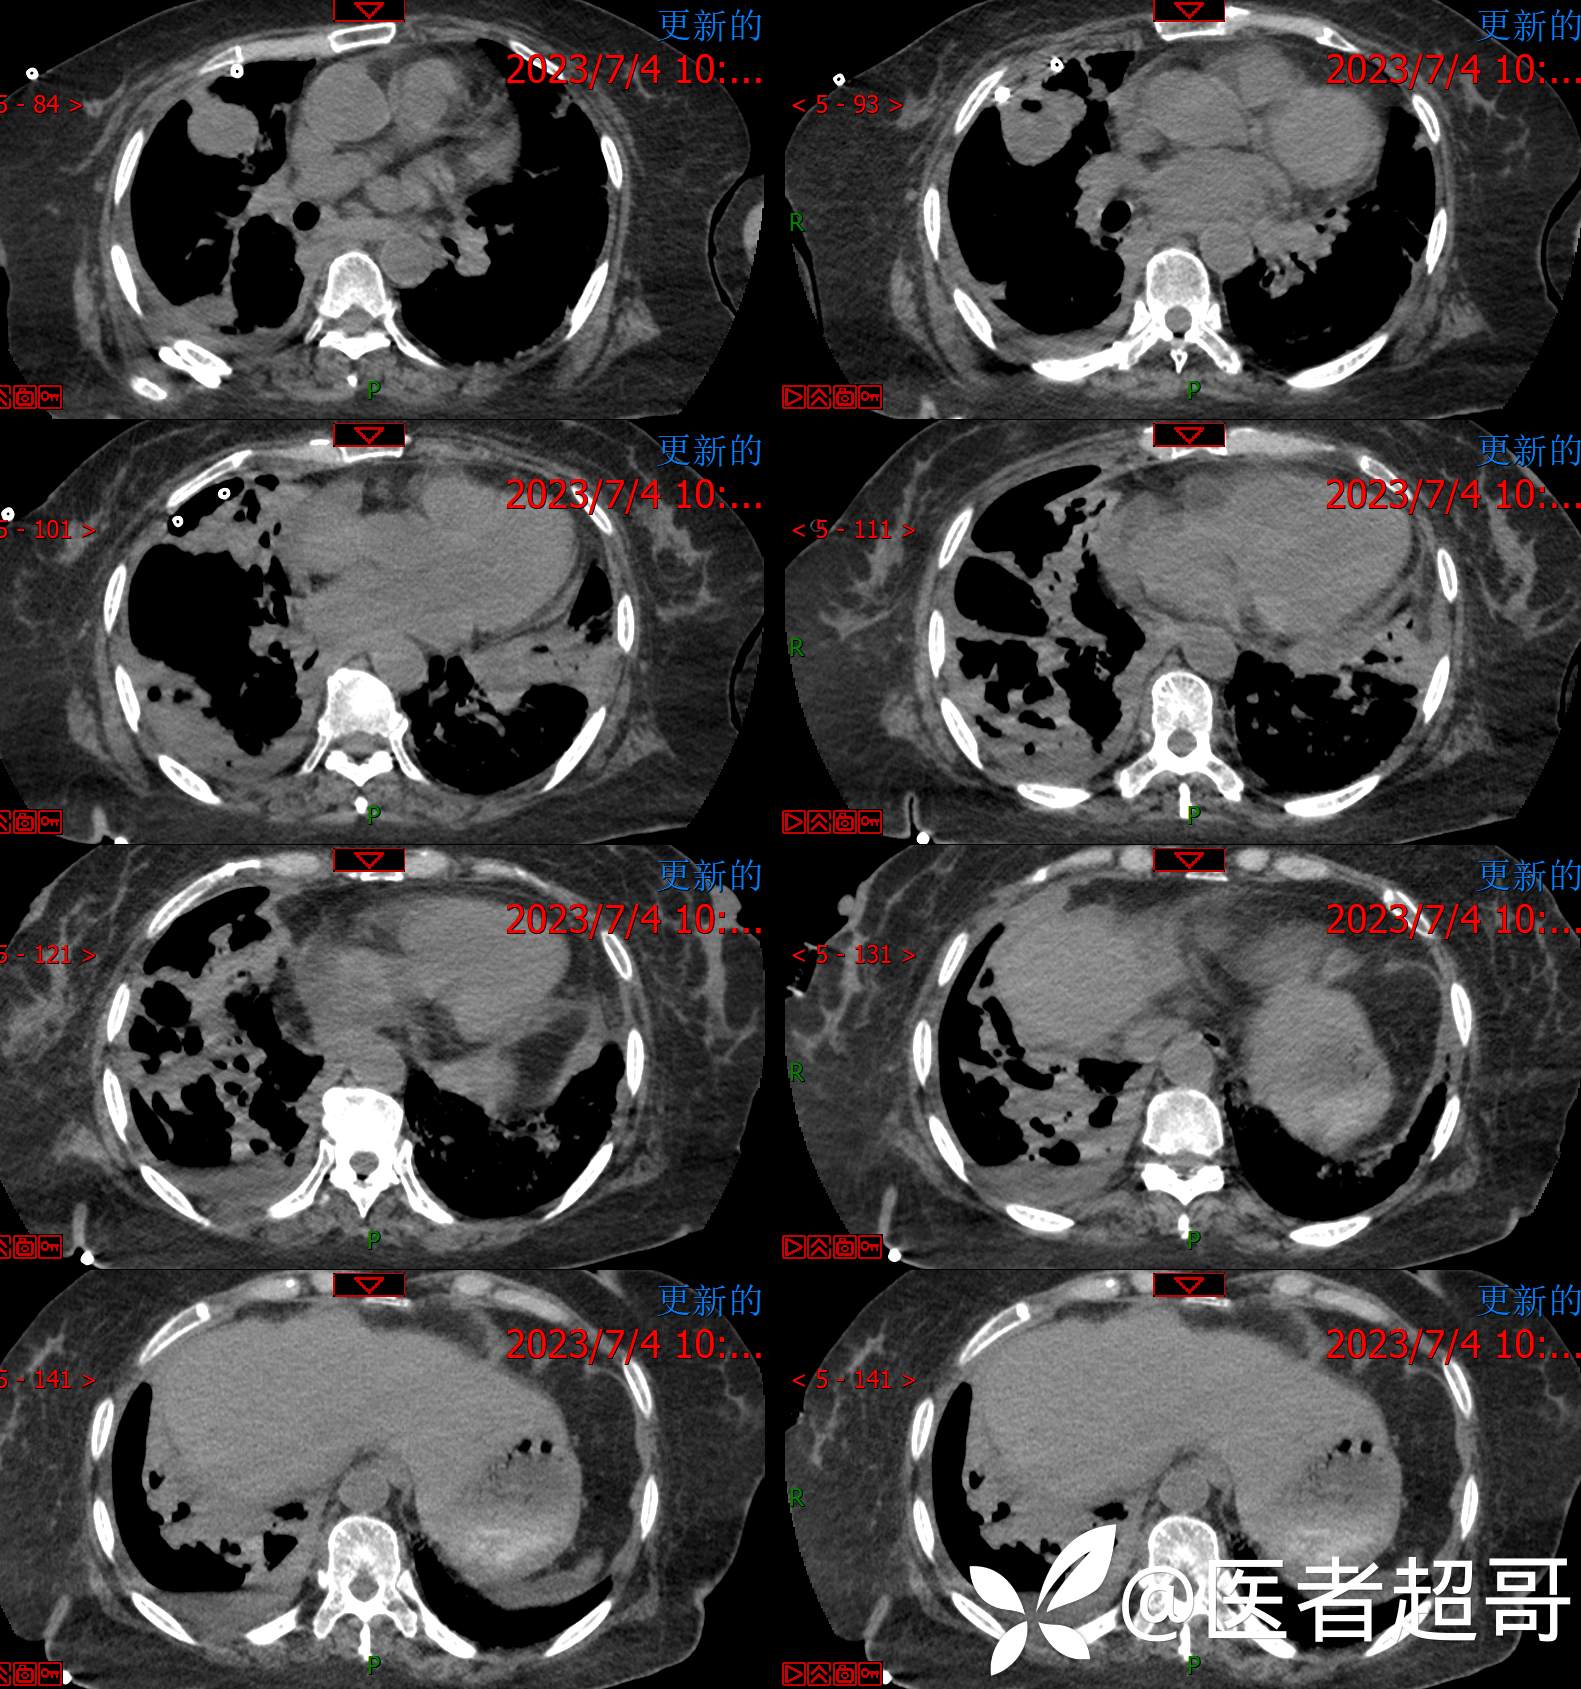

现病史:患者于4年前在神经内科住院期间监测血糖高,随机血糖29.4mmol/l,经治疗好转出院,出院诊断“锥体外系反应 2型糖尿病 感冒”,院外自行口服“二甲双胍 2片 bid,格列吡嗪胶囊 1粒 bid”降糖治疗,平素未规律监测血糖。约3年前感四肢麻木不适,无明显疼痛,无肢体活动障碍,未特殊治疗。7天前出现乏力、憋气不适,伴有流清涕,无发热、寒战,咳嗽不著,有痰不易咳出,食欲减退,无腹痛、腹泻,无恶心、呕吐,患者发病后于当地诊所就诊,监测血糖偏高(具体数值不详),给予输液治疗(具体药物不详),效果欠佳,2天前感乏力、憋气加重,今急来诊,急诊完善胸部CT平扫示:双肺多发肿瘤表现,纵膈淋巴结肿大,心包少量积液,建议三周后复查除外隐匿性骨折;血糖32mmol/l,为求进一步诊疗,门诊以“糖尿病”收入我院。

2023.07.04检查: